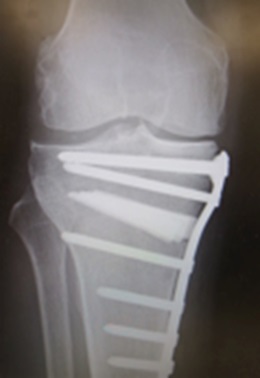

変形性膝関節症に対して、年齢と関節変形のタイプと程度に合わせ、関節温存の高位脛骨々切り術(HTO)、単顆人工膝関節置換術(UKA)と全人工膝関節置換術

(TKA)を患者様の状況に合わせ手術を選択しております。スポーツ外傷膝(半月板損傷、靱帯損傷)に対し、鏡視下手術を積極的に行っております。